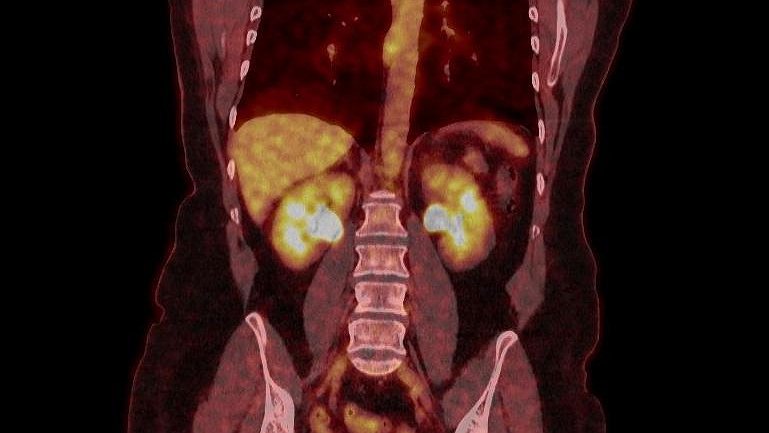

Le Tep-scan de l’hôpital de Dunkerque est une machine très performante pour la recherche de pathologies cancéreuses, cardiologiques, neurologiques.

Il est en service depuis 2017 grâce à douze ans d’acharnement des victimes de l’amiante pour l’obtenir. Il a été payé, non par l’hôpital, mais par le groupement d’intérêt économique auquel participaient les médecins nucléaires qui y exerçaient.